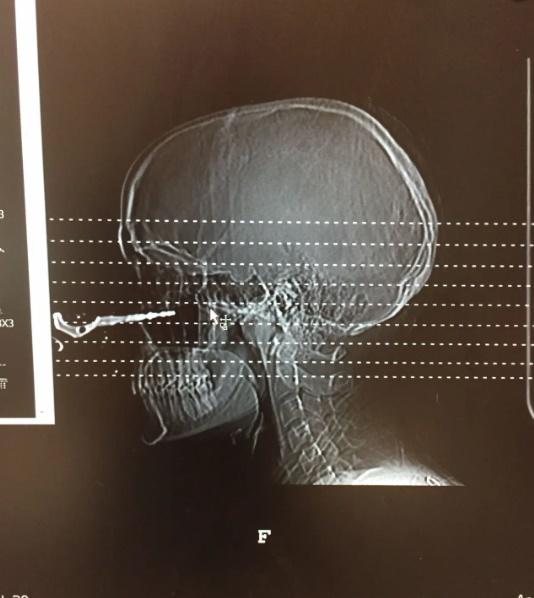

《紐約郵報》(New York Post)報道,事故發生於上月, 24歲女子Renée Lariviere正準備跟朋友出門吃晚餐,當時她的朋友將車匙丟給她,她沒多想就轉身伸手去接,詎料車匙就直插進她的臉頰。

Renée Lariviere指,當下應該是腎上腺素的關係,只覺面被打一下,沒有覺得很痛,但見在場的朋友都驚慌得亂作一團,緊張地著她不要亂動,並致電119求救,她走進廁所查看傷勢,才被鏡中的畫面嚇了一跳。Renée Lariviere說,當時完全無考慮毀容的問題,只擔心自己會否失明。

Renée Lariviere的傷勢在醫院也引起一陣騷動,雖然急症室的醫生們都身經百戰,不過這種傷勢及意外原因實在太離奇,就連其他科的醫生都趕來一睹這「奇景」,更有醫生要求拍照。

幸好Renée Lariviere的眼睛沒有受影響,臉部的恢復狀況亦非常良好,疤痕很淡,看起來就像沒有受過傷一樣。Renée Lariviere說,雖然發生這種意外,但慶幸有驚無險,沒有擊中其他地方。她也特別提醒觀看的網民,日常生活中要格外小心,別亂擲鎖匙。